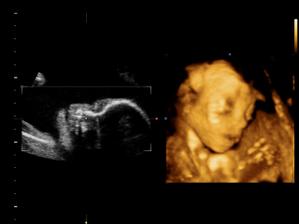

11.05. - (26+5) dnes jedeme na video

video se povedlo, máme asi 6 cca 5 - 10ti vteřinových videíí.Bylo to super. Karolínka se zase mlela jako drak. Je taková živoučká 😀

kontrola - vše v pořádku a máme + 8kg